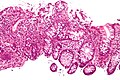

Cryptitis in a rectal biopsy. H&E stain.

Cryptitis is inflammation of an intestinal crypt.

- Intestinal crypts with intraepithelial neutrophils.